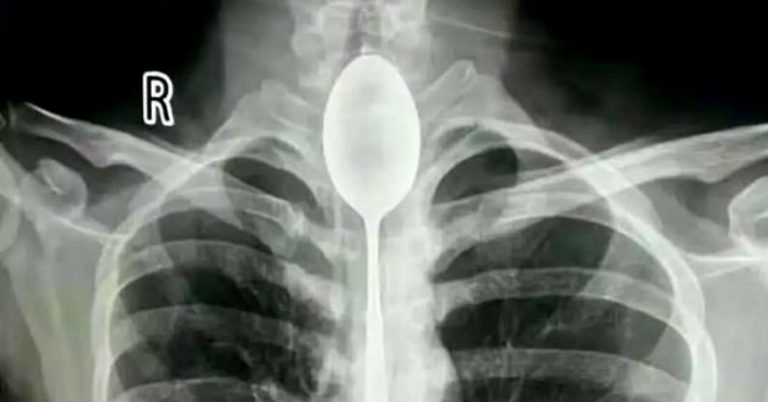

Es lo que ocurrió con un hombre de 26 años que llegó al Hospital General de Xinjiang Meikuang, en China, con una cuchara de 20 centímetros atorada en el esófago. Lo más curioso es que el objeto lo tenía alojado hace un año en su interior, según señala Daily Mail.

"Quedé impactado. Nunca he tenido algo así", dijo Yu Xiwu uno de los médicos que trató al paciente, el cual ya tenía complicaciones en su cuerpo lo que le había provocado una infección en esófago.

Según reconoció el paciente, de apellido Zhang, todo se debió a una apuesta que hizo con unos amigos, donde aseguró que era capaz de tragarse una cuchara. El hombre cumplió su palabra y lo hizo. El problema es que luego no pudo sacársela y anduvo un año con el objeto dentro de su cuerpo.

El hombre señaló que no había acudido antes al hospital porque en ningún momento le había molestado para hablar o comer. Sin embargo, un día recibió un golpe en el pecho lo que le provocó complicaciones derivadas a la cuchara que tenía en esófago.

Afortunadamente los médicos pudieron extraer la cuchara y el hombre se recupera satisfactoriamente.